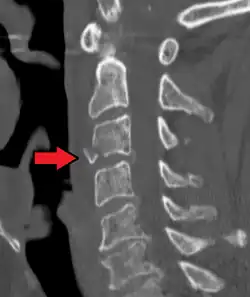

| A fracture of the base of the dens (a part of C2) as seen on CT | |